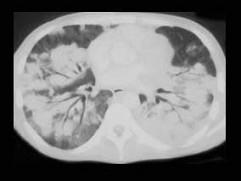

问题 男,27岁,干咳,呼吸困难半月余,有艾滋病病史半年余,请结合CT检查,选出最可能的诊断 ( )

选项 A、矽肺 B、Kaposi肉瘤 C、弥漫型肺癌 D、间质性肺炎 E、粟粒型肺结核

答案 B